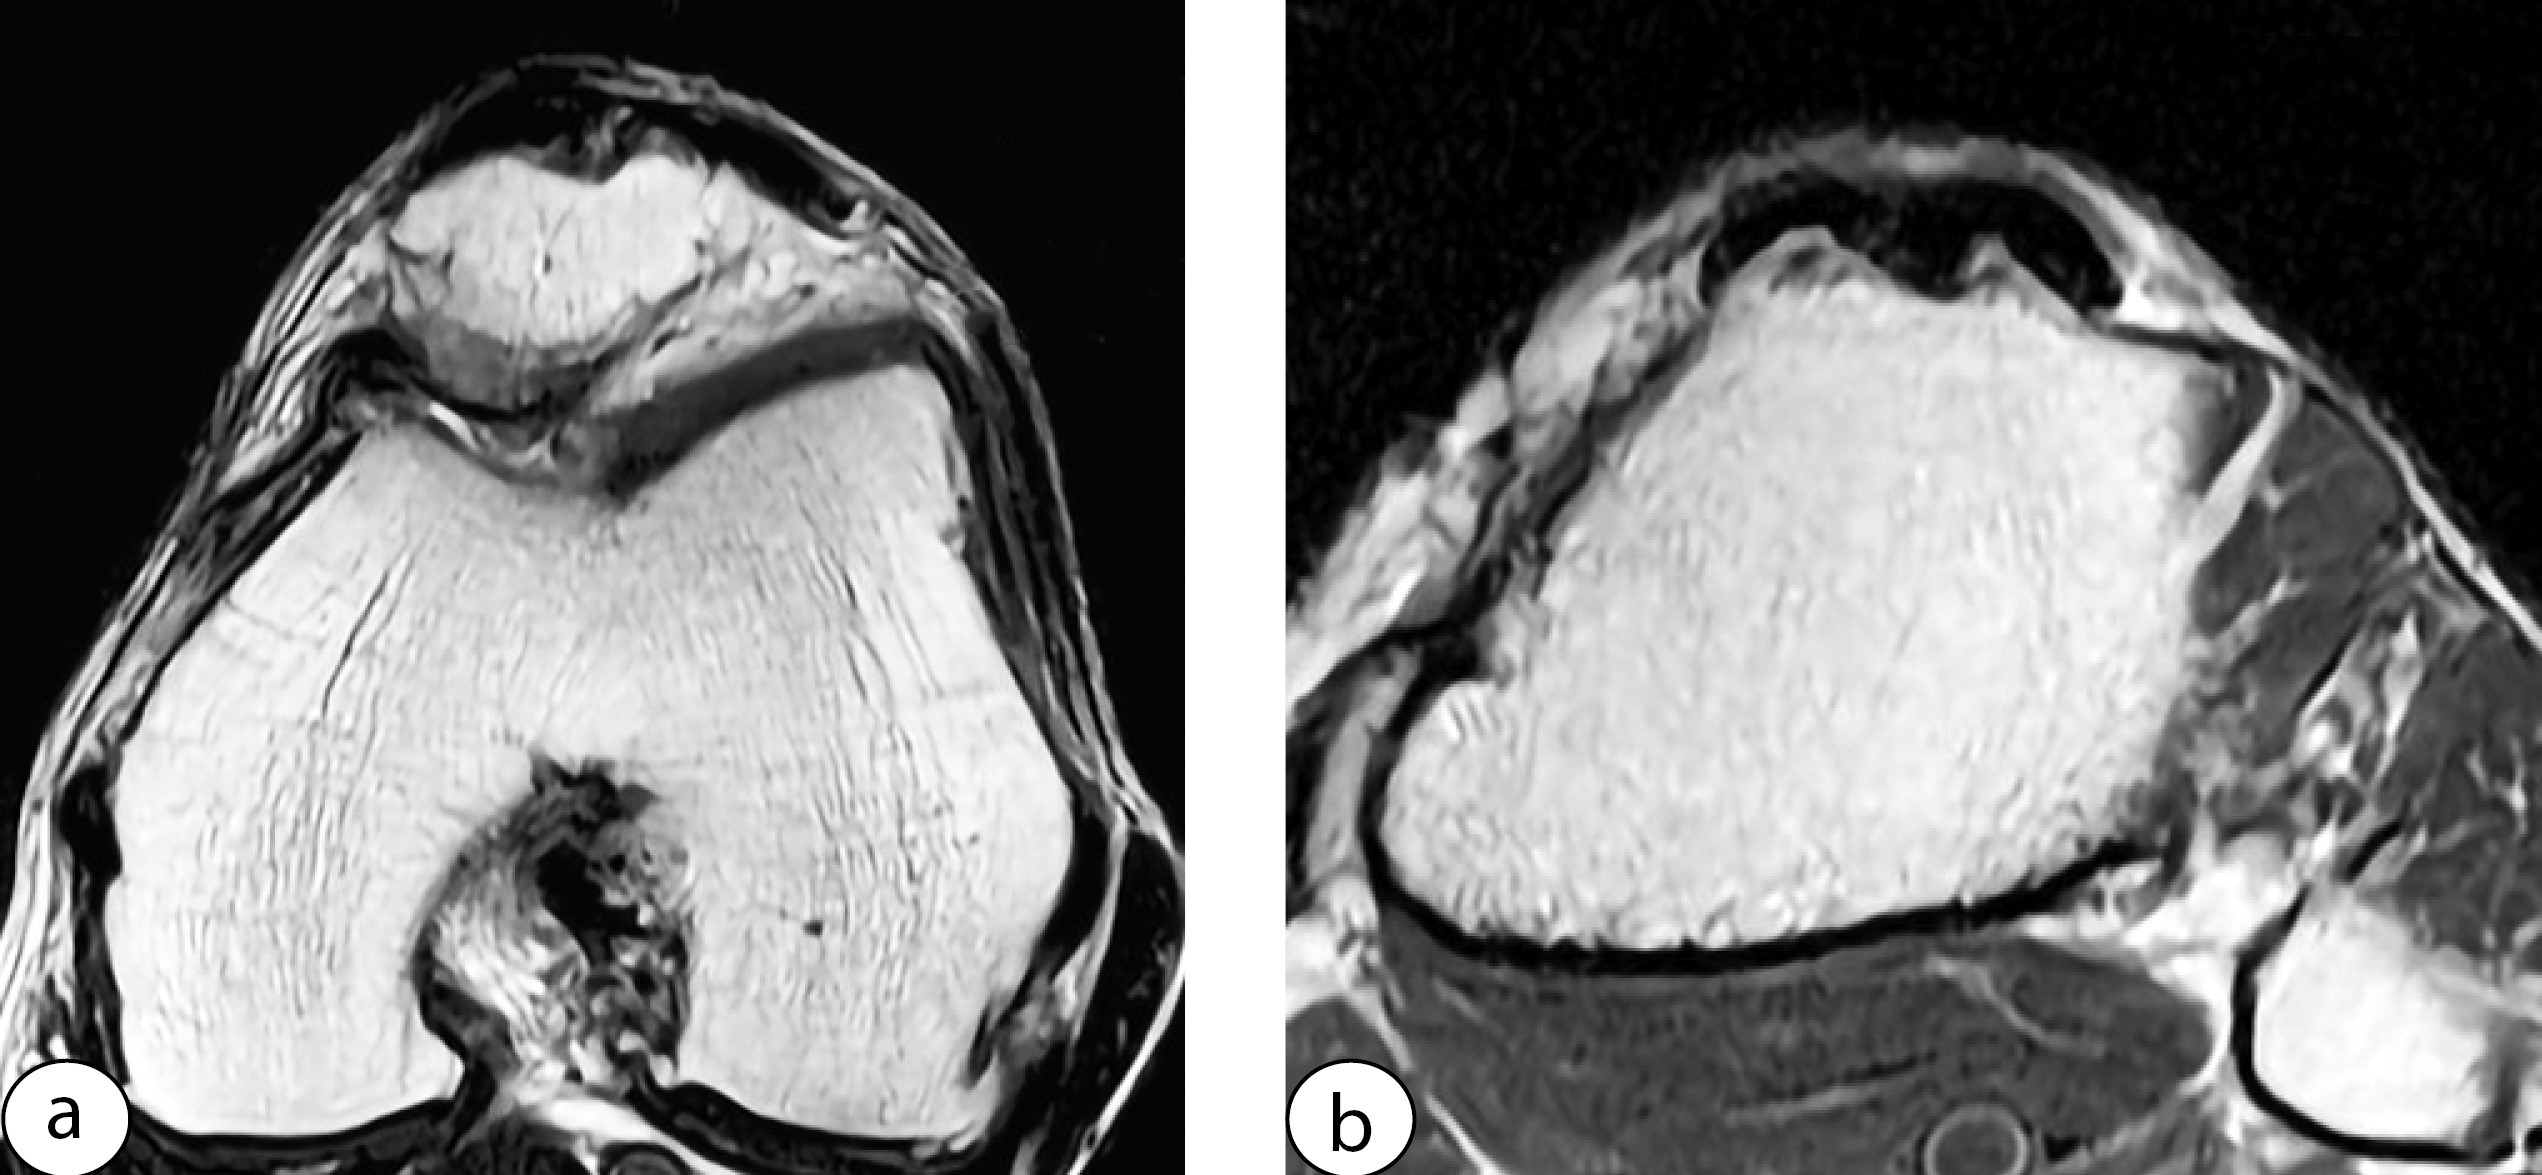

All patients in Group 1 exhibited unfilled bone defects of the patella and tibial tuberosity that persisted until the final follow-up (Figure 3). In the areas where the ligament bundles were sutured, a homogeneous ligament of sufficient width and thickness was observed. In regions where the ligament was not sutured, all patients displayed persistent defects filled with scar tissue resembling the adjacent adipose tissue in density and structure. No signs of defect replacement by tissue resembling ligament were observed even 20 years postoperatively (Figure 4).

Figure 3. Unfilled bone defects at the donor site of the patella (a) and tibial tuberosity (b) in a patient from Group 1 at 20-year follow-up

Figure 4. The unsutured segment of the patellar tendon filled with scar tissue resembling the adjacent adipose tissue in density and structure (a); the sutured segment appears homogeneous, broad enough, and slightly thickened (b) in a patient from Group 1 at 20-year follow-up